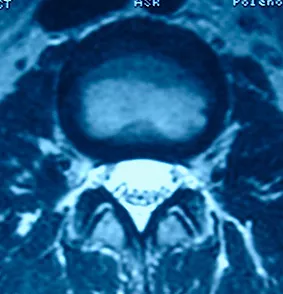

1. МРТ с высокой напряженностью магнитного поля (1,5 – 3,0 Тесла) – основной метод диагностики и нейровизуализации стеноза позвоночного канала.

Норма

Стеноз